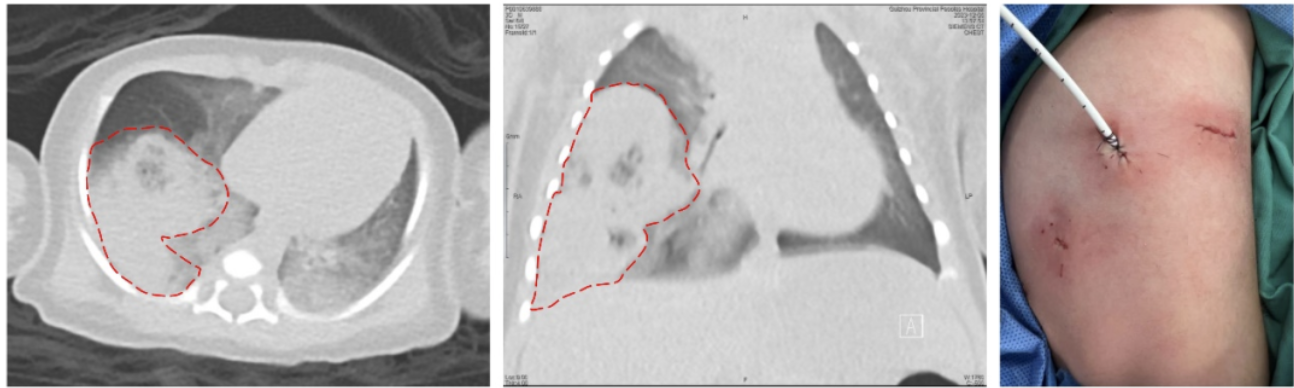

图一、图二 红色虚线指示右肺下叶病变;图三为患儿微创手术切口。

在上海儿童医学中心贵州医院儿童普胸外科、新生儿科、麻醉科、手术室团队的密切配合下,由李飞副主任医师为患儿顺利完成了胸腔镜下右肺下叶基底段切除术,小辛术后病情稳定。

据李飞副主任医师介绍,新生儿病情变化快,对手术打击承受能力弱,进行胸科手术风险巨大,实施手术面临很大的挑战。查阅文献及相关报道,小辛的手术为我省第一例新生儿胸腔镜肺段切除手术。为小辛成功实施手术既体现了上海儿童医学中心贵州医院多学科过硬的技术本领,也彰显了上海儿童医学中心贵州医院作为儿童区域医疗中心的责任与担当!